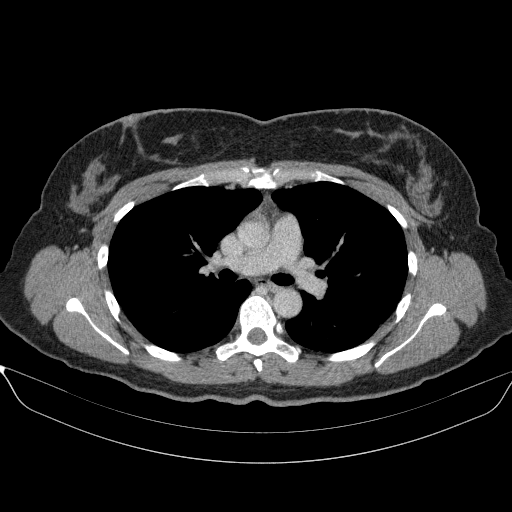

Targeted Slice 70 - Mediastinum Window Analysis (Generated vs Real Venous)

0.741

Mediastinum SSIM

34.8

Mediastinum RMSE

13.6

Mediastinum MAE

Average Mediastinum Window Metrics Across All Slices (170 slices) - Generated vs Real Venous

0.728

Mediastinum SSIM (Avg)

35.8

Mediastinum RMSE (Avg)

14.6

Mediastinum MAE (Avg)

Generated VENOUS CT scan (A→B translation)

No window - Raw intensity values